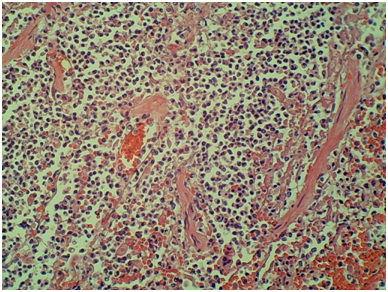

Autopsy of the decedent demonstrated disseminated invasive aspergillosis with multiple cavitating, necrotic, hemorrhagic, friable, soft, red and yellow-white lesions in both lungs (Figure 1), severe pericardial and pleural adhesions of the lungs, and hemorrhagic and cavitating soft masses in cerebrum (Figure 2) and cerebellum. Histologic examination of lungs revealed necrotizing pneumonia with sharply delineated rounded foci with hemorrhagic borders. Alveoli are filled with neutrophilic exudates with breakdown of the alveolar septa and formation of abscesses (Figure 3). In the brain there were multiple cavitating, hemorrhagic, friable, necrotic, soft yellow lesions. Microscopic sections demonstrated red blood cells and inflammatory cells in the involved area (Figure 4). GMS staining showed septate hyphae that branched dichotomously at acute angles, consistent with Aspergillus fungus (Figures 5&6). The fungal colonies were confined to the necrotic material and appeared as branching, slender, septate hyphae (Figures 5&6). There was no evidence of infection of the heart, pancreas, kidneys, liver, spleen, or adrenal glands.